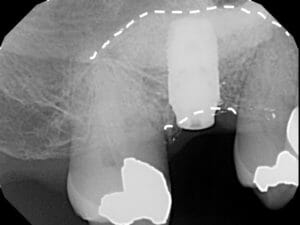

Sinus Graft

One of the most common areas for bone grafting for dental implants in Jacksonville is the upper back jawbone. When our upper molars are removed, there is often only a small amount of bone between the teeth and the sinus cavity. During bone healing, even with a ridge preservation, the sinuses tend to grow into this space, further reducing the available bone for implants. If need be, Dr. Kuznia and Dr. Storch can perform a Sinus Graft, or, enter the sinus cavity through a window about the size of a dime to add a bone graft to this area. If you are considering getting dental implants in Jacksonville, Orange Park, or the surrounding areas, visit one of our four locations today!